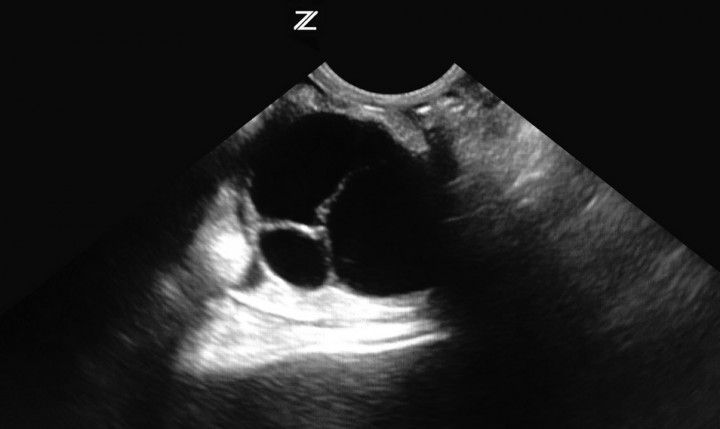

El método diagnóstico de elección en este caso es la ecografía.[ Bean AD: Ovarian cysts in the guinea pig (Cavia porcellus). Vet Clin North Am Anim Pract Exot. 2013; 16(3): 757- 76. [PubMed] ] Con el fin de minimizar el estrés al animal, se realiza una sedación con 0,3 mg/Kg intramuscular (IM) de midazolam[ Carpenter JW: Rodents in Exotic animal formulary, fourth edition. Missouri, Elsevier Editorial, 2012; 480- 493. ] (Midazolam Normon® EFG 15 mg/3 ml- Lab. Normon S.A., Madrid). En la ecografía abdominal se observa la presencia de dos quistes ováricos: de 5 cm de diámetro el derecho, y 7 cm el izquierdo (Fig. 3). Se aprovecha la sedación para realizar una punción ecoguiada de los quistes, consiguiendo extraer 140 ml de líquido. Esto se realiza con el fin de aliviar las posibles molestias que pueda presentar el animal, por la presión que ejercen los quistes dentro de la cavidad abdominal, hasta programar la cirugía, ya que es el tratamiento de elección en estos casos.[ Bean AD: Ovarian cysts in the guinea pig (Cavia porcellus). Vet Clin North Am Anim Pract Exot. 2013; 16(3): 757- 76. [PubMed] , Pilny A: Ovarian cystic disease in guinea pigs. Vet Clin North Am Anim Pract Exot. 2014; 17(1): 69- 75. [PubMed] ]

<p>Quiste ovárico izquierdo (caso 1).</p>

Figura 3

Quiste ovárico izquierdo (caso 1).